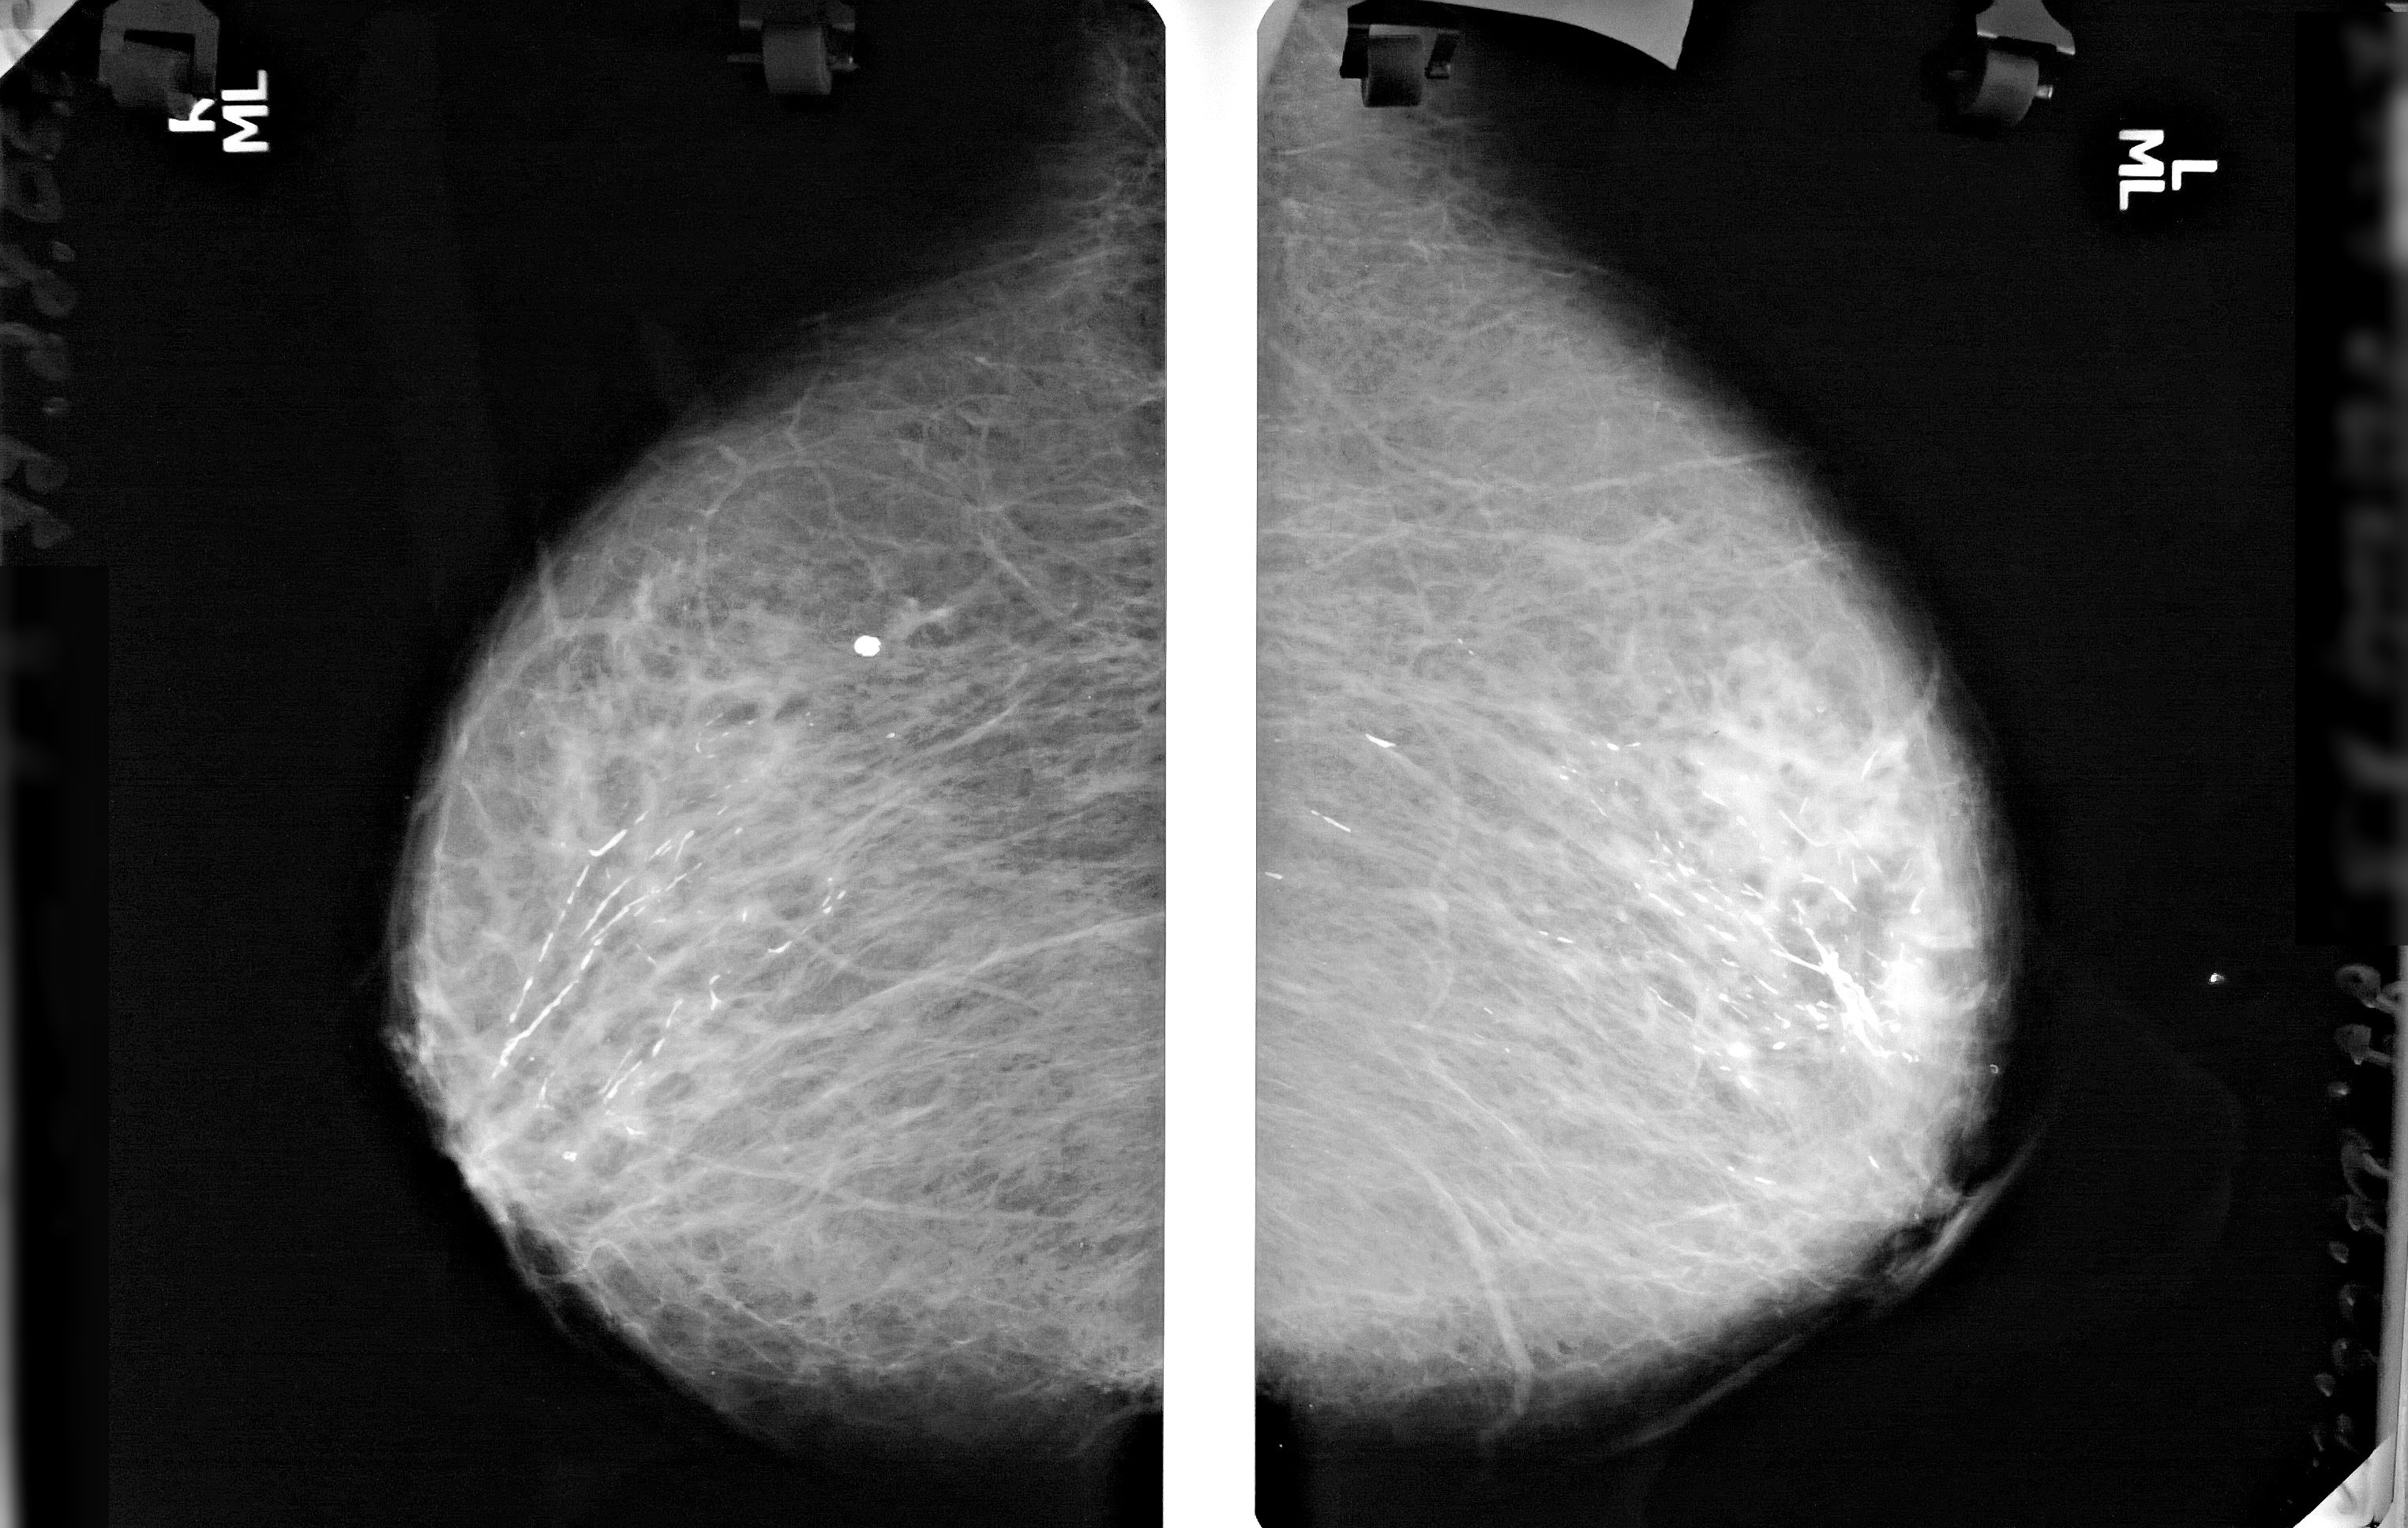

Фиброзно кистозная мастопатия маммограмма